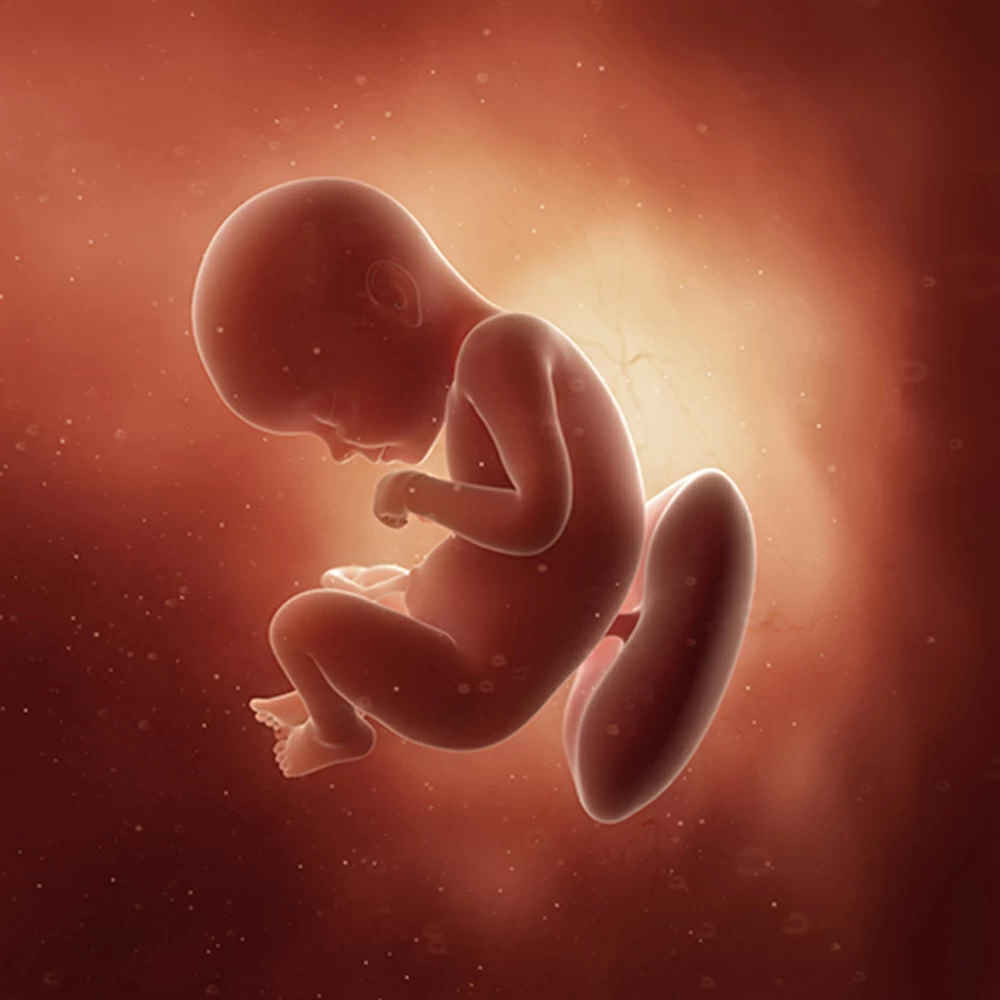

Неделя № 30

Масса тела увеличивается до 1300-1350 грамм, рост остается примерно тем же – около 38-39 см.

Постоянно накапливается подкожная жировая клетчатка, расправляются кожные складки. Ребенок приспосабливается к недостатку места и принимает определенное положение: сворачивается, руки и ноги скрещиваются.